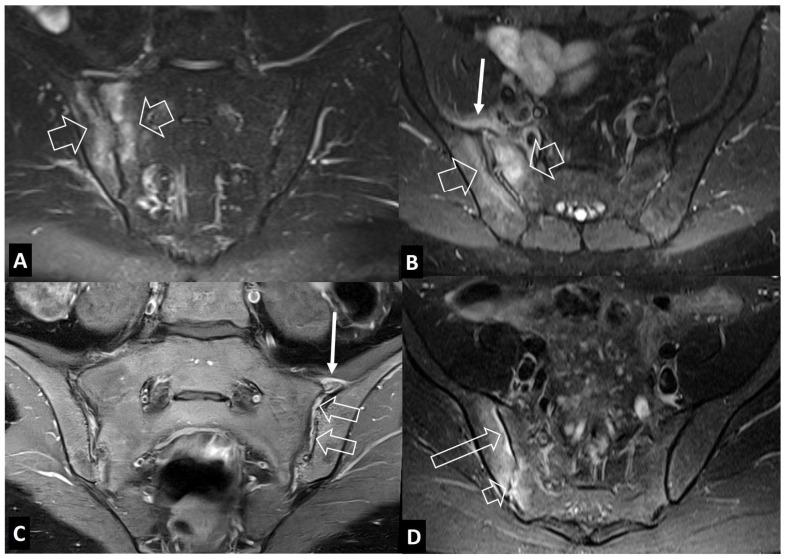

A series of conditions can mimic musculoskeletal infections on imaging, complicating their diagnosis and affecting the treatment. Depending on the anatomical location, different conditions can manifest with clinical and imaging findings that mimic infections. Herein we present a wide spectrum of the musculoskeletal disorders of the axial skeleton, long bones, peripheral joints, and soft tissue that may manifest as infectious processes, and we focus on the potential mimics of osteomyelitis, septic arthritis, and infectious spondylodiscitis that are common in clinical practice. We present the typical imaging characteristics of each musculoskeletal infection, followed by mimicking conditions.

一系列病症在影像学上可模拟肌肉骨骼感染,使诊断复杂化并影响治疗。根据解剖位置的不同,不同病症可表现出类似感染的临床和影像学表现。在此,我们展示了轴向骨骼、长骨、外周关节和软组织的广泛肌肉骨骼疾病,这些疾病可能表现为感染过程,并且我们重点关注临床实践中常见的骨髓炎、化脓性关节炎和感染性脊椎间盘炎的潜在模仿病症。我们介绍了每种肌肉骨骼感染的典型影像学特征,随后是模仿病症。